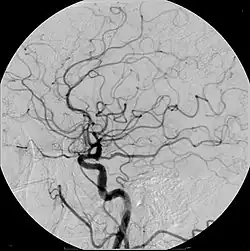

An iodine-based contrast in cerebral angiography

Iodinated contrast contains iodine. It is the main type of radiocontrast used for intravenous administration. Iodine has a particular advantage as a contrast agent for radiography because its innermost electron ("k-shell") binding energy is 33.2 keV, similar to the average energy of x-rays used in diagnostic radiography. When the incident x-ray energy is closer to the k-edge of the atom it encounters, photoelectric absorption is more likely to occur. Its uses include: